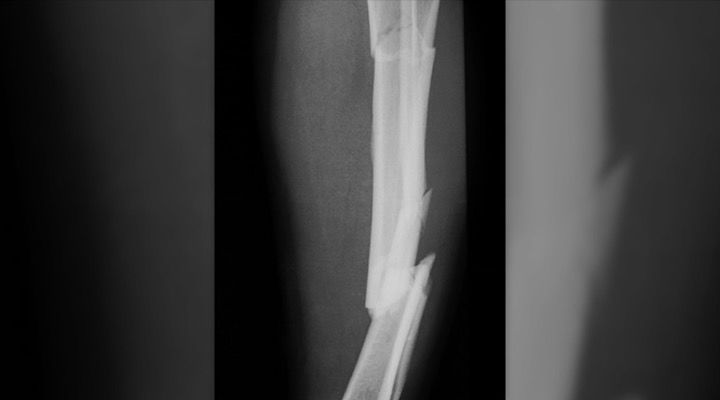

Flopped Foot

After giving Robinson some pain medication, the ambulance crew was able to get the boot off. After removing it they knew just how bad the break was. “When they did my foot just flopped to the side in a horrible shape,” Robinson said.